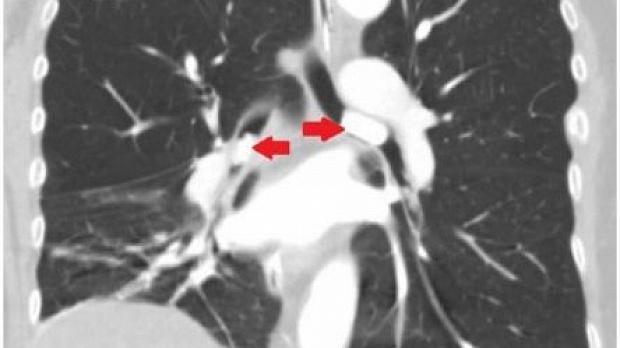

Пациентка обратилась с жалобами на прогрессирующую одышку и кашель в течение месяца. Рентгенография органов грудной клетки показала изменения в правом легком с небольшим количеством жидкости в правой плевральной полости. Но при компьютерной томографии грудной клетки инфильтрации или других изменений легочной ткани не обнаружено. Пациентке назначена эмпирическая антибактериальная терапия. При исследовании мокроты выявлен рост непатогенной флоры. Состояние пациентки продолжало ухудшаться, что потребовало интубации трахеи и искусственной вентиляции легких. При повторной КТ грудной клетки выявлены гиперденсные образования в просвете левого главного (размер 2,2 см) и промежуточного бронхов (размер 1,5 см), обтурирующие их (рис. 1, 2).

Рисунок 2 [1].